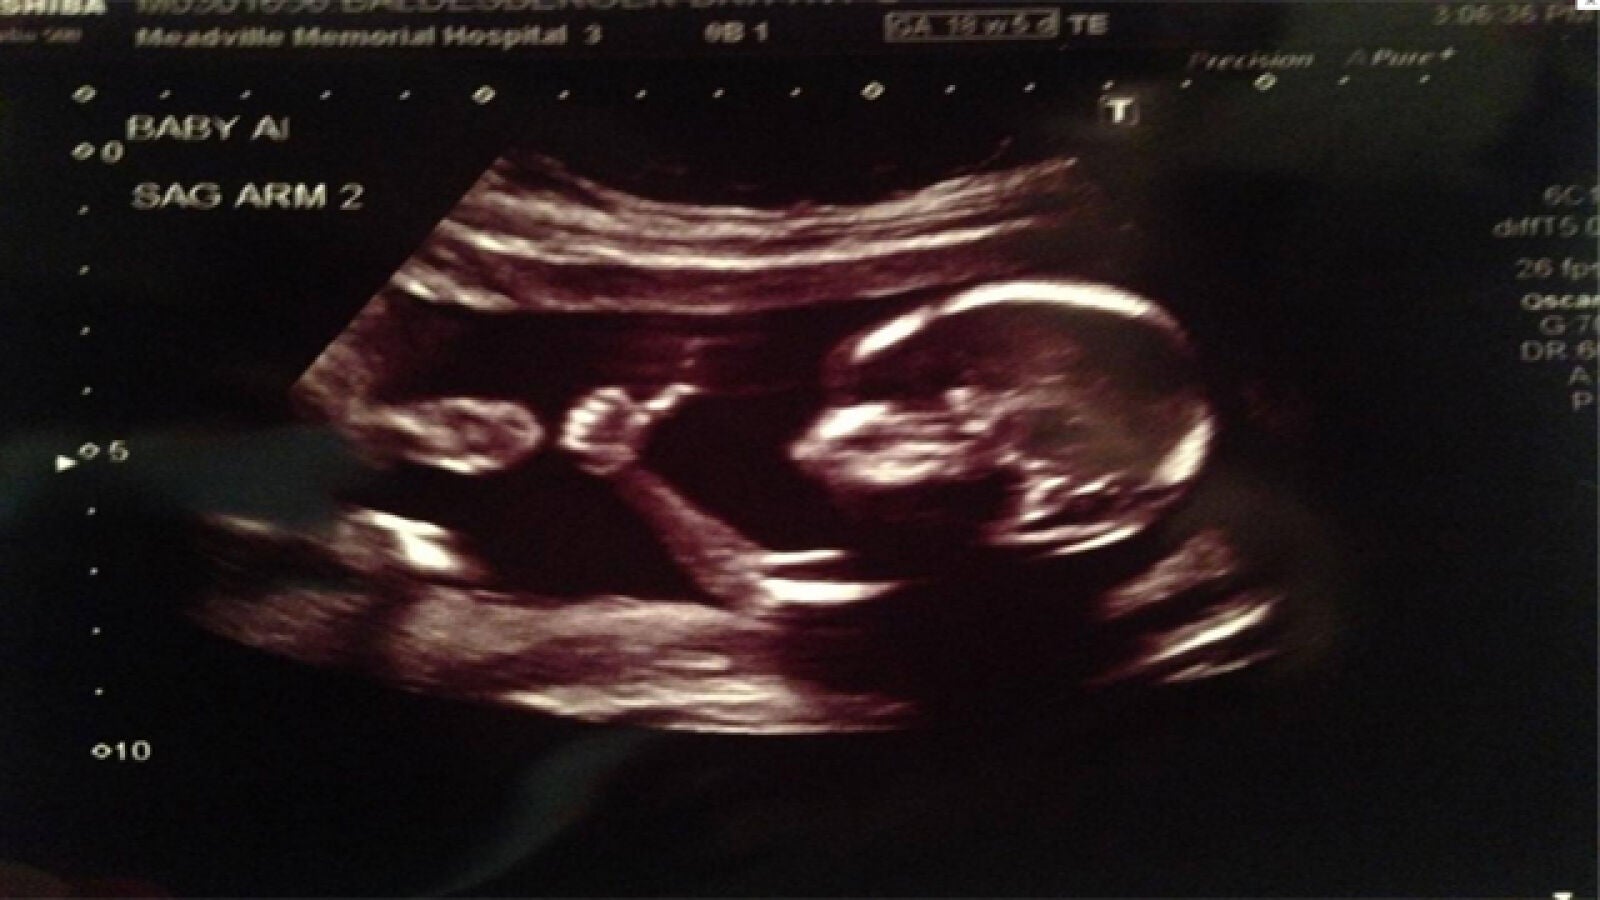

Un feto de 18 semanas levanta el pulgar haciendo el gesto de OK

En una ecografía rutinaria y con sólo 18 semanas un feto levantó el pulgar con la expresión de 'todo va bien' ante el asombro de sus padres. Hasta el momento más de dos millones de internautas han visto la imagen en el perfil de 'Reddit' del progenitor en solo 24 horas.

Solemos entender el gesto de un pulgar hacia como la expresión de que 'todo va bien'. Con tan sólo 18 semanas un bebé realizó este gesto ante sus papás en una ecografía según publica el diario 'The Independent'.

Ante este gesto, poco habitual para un feto, el padre de la criatura colgó la imagen en su perfil de la red social 'Reddit', donde más de 2 millones de personas ya han visto la imagen. La sorpresa de los internautas fue mayor cuando descubrieron que estos padres estaban esperando gemelos, muchos se preguntaron si el otro bebé estaba de acuerdo con el gesto de su hermano viendo la cómoda postura en la que se encontraba el primero.